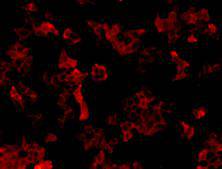

Immunofluorescent staining of Hela cells using anti-Neuropilin 1 Mouse mAb (Cat. # M0910-5).